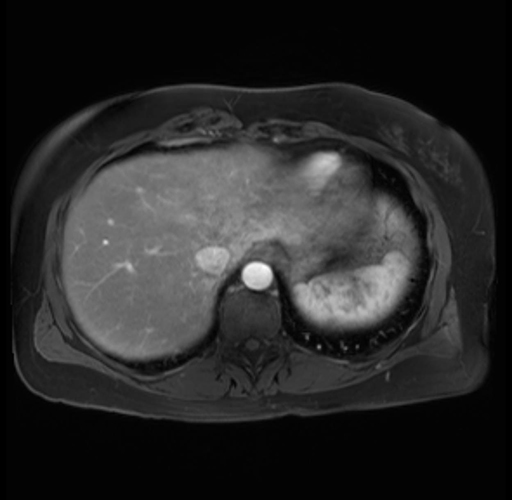

Imaging Analysis

Look through the patient's CT scan to identify any areas of concern for the necessary procedure.

Based on your CT findings, which issue(s) are present and would give reason for "planned slowing down moment(s)" in this case?